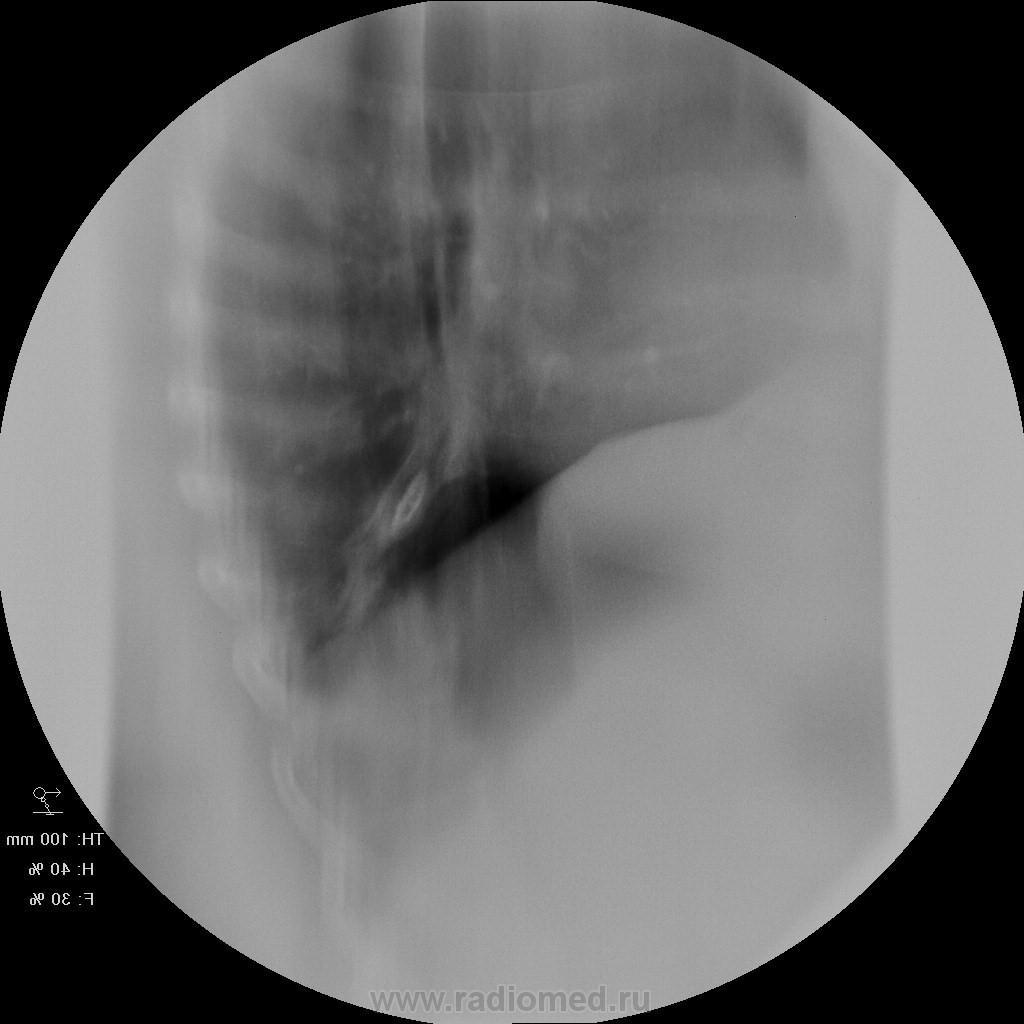

Женщина 50 лет поступила а пульмонологическо отделение с клиникой и диагнозом обострения бронхита. 15 лет назад перенесла тяжелую пневмонию нижней доли правого легкого. после этого находили выше указанные изменения в легих и наблюдали у фтизиатров. со слов " дисковидная туберкулема" или что-то вроде этого. на флю - картина на протяжении всего времени стабильная. на фбс - нижнедолевой бронх для эндоскопа не проходим, контактная кровоточивость, взята биопсия. прошу совета. какие будут мнения? выставляю только томо - снимки обычные не снимал. но картина на них подобная. по анализам без особенностей. не худела...

так как обозвать эту линзу с плотностью кальцинта? я вижу ателектаз-гиповентиляцию нижней доли, на фоне чего - эта "линза" - постпнемонический фиброателектаз?

А это не может оказаться обычным бронхолитиазом?

а причина этого "камня"? мог ли он образоваться после даже тяжелой пневмонии? что еще так может выглядеть? но главное для меня - добро или зло? я склоняюсь к какому то доброкачественному процессу, конечно, основываясь на стабильности картины на потяжении очень долгого времени...

Обычно бронхолитиаз возникает в результате пролежня кальцинированного лимфоузла в корне легкого.

Мне очень импонирует мысль о БРОНХОЛИТИАЗЕ....